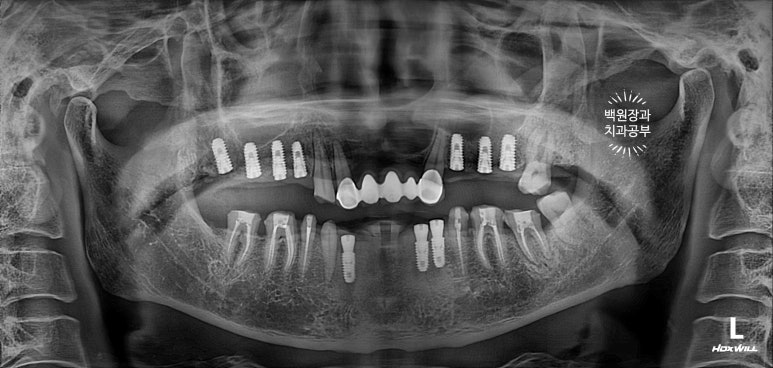

노란색 동그라미로 표시한 위턱 어금니는 당연히 틀니 혹은 임플란트로 만들어주어야 합니다.

환자분은 고정식 치료를 원하셨기 때문에, 위턱의 빈 자리에 전체 임플란트 수술을 계획하였습니다.

아래 어금니들은 위 어금니가 없는 사이에 너무 많이 정출되어 있었어요.

치아가 교합평면 (occlusal plain)을 기준으로 보았을 때 너무 튀어나왔기 때문에 깎아 내릴 필요가 있었어요.

(녹색 화살표로 표시해 둔 치아들은 3-4mm 이상 정출되어 있었어요. 대합치가 없기 때문이죠.)

다른 치과에서는 아래 어금니도 다 뽑고 임플란트를 하자고 하셨었는데, 치아들의 흔들거림이 없었기에 신경치료와 크라운치료로 아래 어금니들을 최대한 활용해보기로 계획했습니다.

정말 뿌리만 남았던 아래 앞니는 제거했습니다.

위턱 어금니가 없어 빈 자리에 임플란트 1차 수술을 하였습니다.

임플란트가 많이 필요한 이런 전체 구강재건 케이스의 경우는, 이를 뽑거나 임플란트를 심는 수술적인 치료가 선행됩니다. 이번 환자분은 아래 앞니가 너무 짧았고, 뿌리끝에 염증까지 있었기에 재신경치료를 하지 않고 발치하였습니다. 그리고 위턱뼈에는 총 7개의 임플란트를 심어드렸어요.

아래 앞니가 닳아 없어지도록 사용하셨던 것으로 보아, 교합력이 상당하다고 생각되기에 임플란트는 최대한 두꺼운 것을 심어드렸습니다.

임플란트가 얇아지면 추후에 임플란트 찢어짐 (또는 파절) 가능성이 높아지기에 최대한 많이, 그리고 두꺼운 임플란트를 심어드려야 합니다.